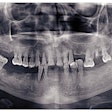

One report, which also includes a literature review, cites a 38-year-old who had developed a low-grade chondroblastic osteosarcoma of the right maxilla 11 months after receiving a titanium dental implant. She was treated with systemic chemotherapy and then a maxillary resection (JADA, August 2008, Vol. 139:8, pp. 1052-1059).

In the second article, the authors cite the case of an 81-year-old who developed a squamous cell carcinoma (SCCa) adjacent to an implant. The woman had a history of oral lichen planus (OLP). She developed an in situ SCCa on the left mandibular ridge, which was edentulous, three years after undergoing implant-supported reconstruction. A year after a marginal mandibular resection, a recurrence developed over the resected area, requiring segmental mandibulectomy (JADA, August 2008, Vol. 139:8, pp. 1061-1065).

As the use of endosseous implants continues to expand, careful follow up after procedures also needs to keep pace, the researchers found. A routine checkup every three months is the goal for an industry standard, keeping in mind that recurrent primary malignancy can masquerade as benign peri-implant complications such as peri-implantitis.